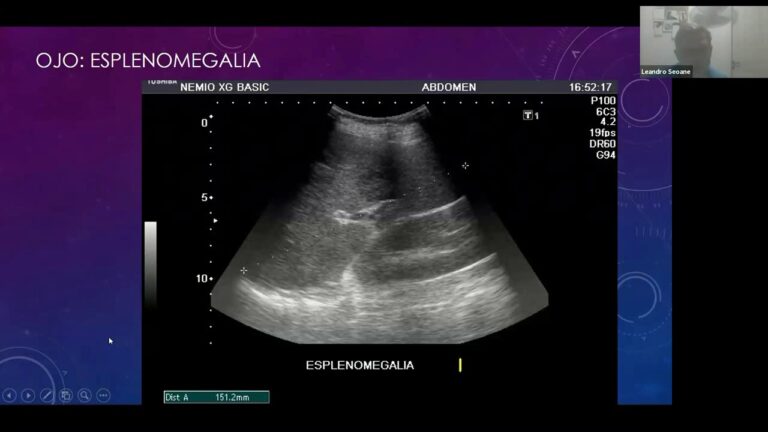

En algunos casos, se puede requerir la realización de estudios de imagen, como radiografías o ecografías, para visualizar el tracto urinario y detectar obstrucciones o anomalías estructurales. Estas pruebas combinadas permiten a los veterinarios establecer un diagnóstico preciso y desarrollar un plan de tratamiento eficaz, asegurando así el bienestar del animal en crisis.

Otra estrategia crítico es la realización de pruebas diagnósticas complementarias. Estas incluyen análisis de sangre, radiografías y ultrasonidos, que proporcionan información valiosa sobre el estado interno del animal. La elección adecuada de estas pruebas, junto con la interpretación experta de los resultados, es esencial para confirmar o descartar enfermedades. Así, se asegura un enfoque más completo y fundamentado en el tratamiento del paciente.

El manejo de estas urgencias implica un enfoque sistemático que incluye la evaluación clínica, pruebas diagnósticas y un plan de tratamiento adecuado. Es crítico realizar un examen físico exhaustivo y considerar pruebas como análisis de orina y ecografías para determinar la causa subyacente. Al implementar un protocolo de urgencias bien estructurado, los veterinarios pueden ofrecer un cuidado eficaz y oportuno, mejorando así las posibilidades de recuperación y calidad de vida de las mascotas afectadas.